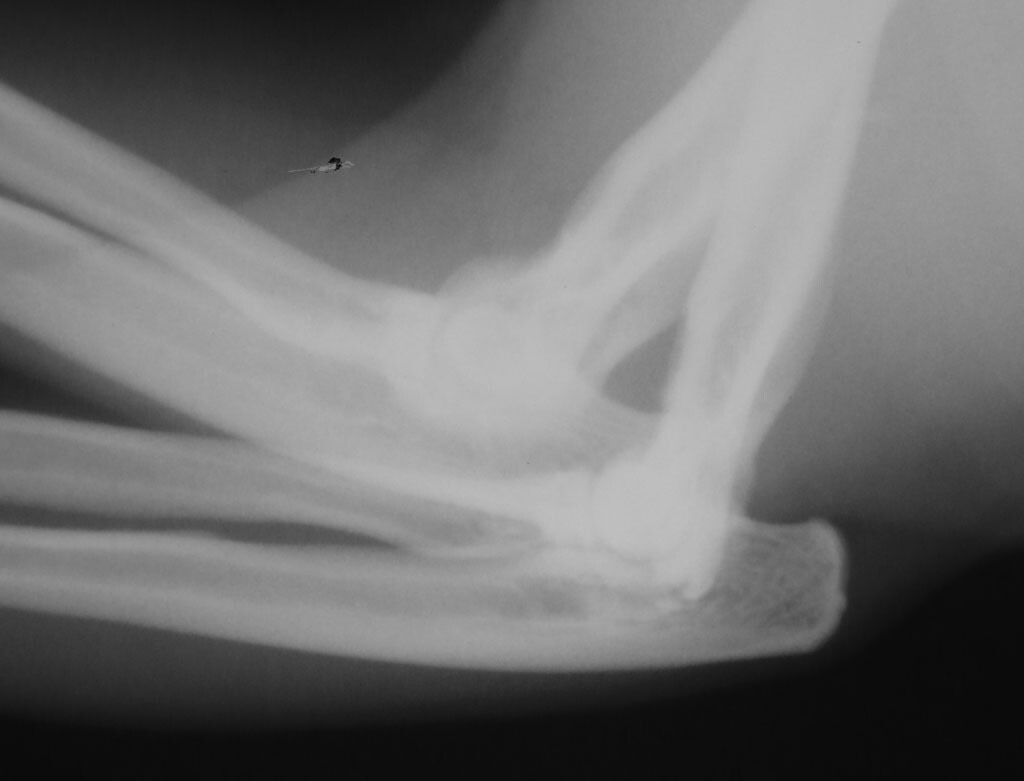

經過檢查牠的右前腳有一顆不小的腫瘤

等待了一週的切片報告後......

確定是惡性的

而且X光片上有霧霧的現象

醫生研判已有蔓延至骨頭

所以牠必需要截肢!!!